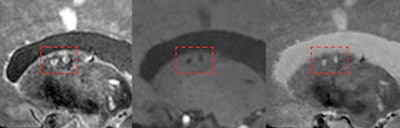

7-tesla MRI can detect the total burden of larger and smaller infarcts, including small microinfarcts in the deep gray matter (shown here inside red frames). Images are courtesy of Dr. Jeroen Hendrikse and originally appeared in ECR Today on 28 February 2019.Outside of gadolinium, a clinical session on 7-tesla MRI drew an overflowing crowd interested in hearing the experiences of a handful of clinical sites around the world using ultrahigh-field MRI. The higher signal-to-noise ratio of 7-tesla MRI and other technical benefits offer new insights into neuro and musculoskeletal imaging. Cardiovascular and abdominal MRI are thought to be the next applications to benefit from 7-tesla scanning.